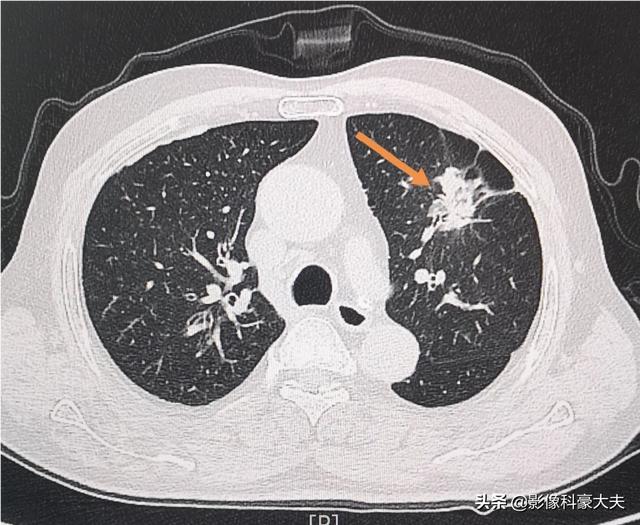

Nous avons rencontré aujourd'hui un patient souffrant d'une hypertrophie de la prostate et de difficultés à uriner en vue d'une intervention chirurgicale. L'examen préopératoire de routine doit être approfondi afin d'exclure toute maladie grave, ce qui a conduit à la découverte d'un adénocarcinome du côté gauche des poumons, alors qu'il n'a encore présenté aucun symptôme pulmonaire.

À ce stade, il n'est pas possible de procéder d'abord à une opération de la prostate, il faut retirer le cancer du poumon de toute urgence !